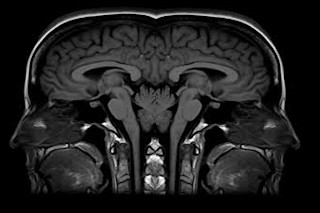

在大多数人中,语言功能位于大脑的左半球。大约4%的右撇子表现出右半球或混合半球的语言侧化,而非右撇子中,这一比例约为30%。